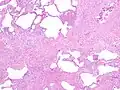

Appearance of honeycomb change in a surgical lung biopsy at low magnification. The dilated spaces seen here are filled with mucin. Hematoxylin-eosin stain, low magnification. -